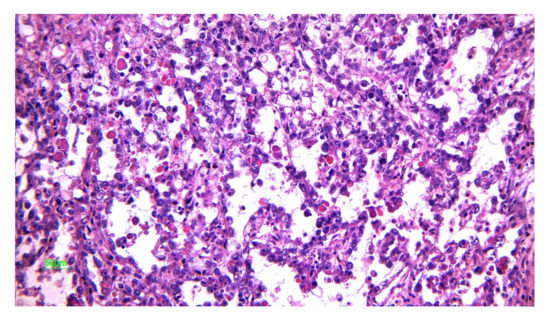

2.4. Immature Teratoma

2.4.2. Microscopic Features